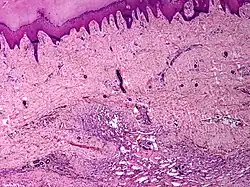

Skin angiomatosis

Angiomatosis is a non-neoplastic condition[1] characterised by nests of proliferating capillaries arranged in a lobular pattern, displacing adjacent muscle and fat.[2] It consists of many angiomas.[3]

It is a vascular malformation wherein blood vessels proliferate along with accompanying mature fat and fibrous tissue, lymphatics and sometimes nerves.[2] They may involve skin, subcutaneous tissue, skeletal muscle and occasionally bone.[2]